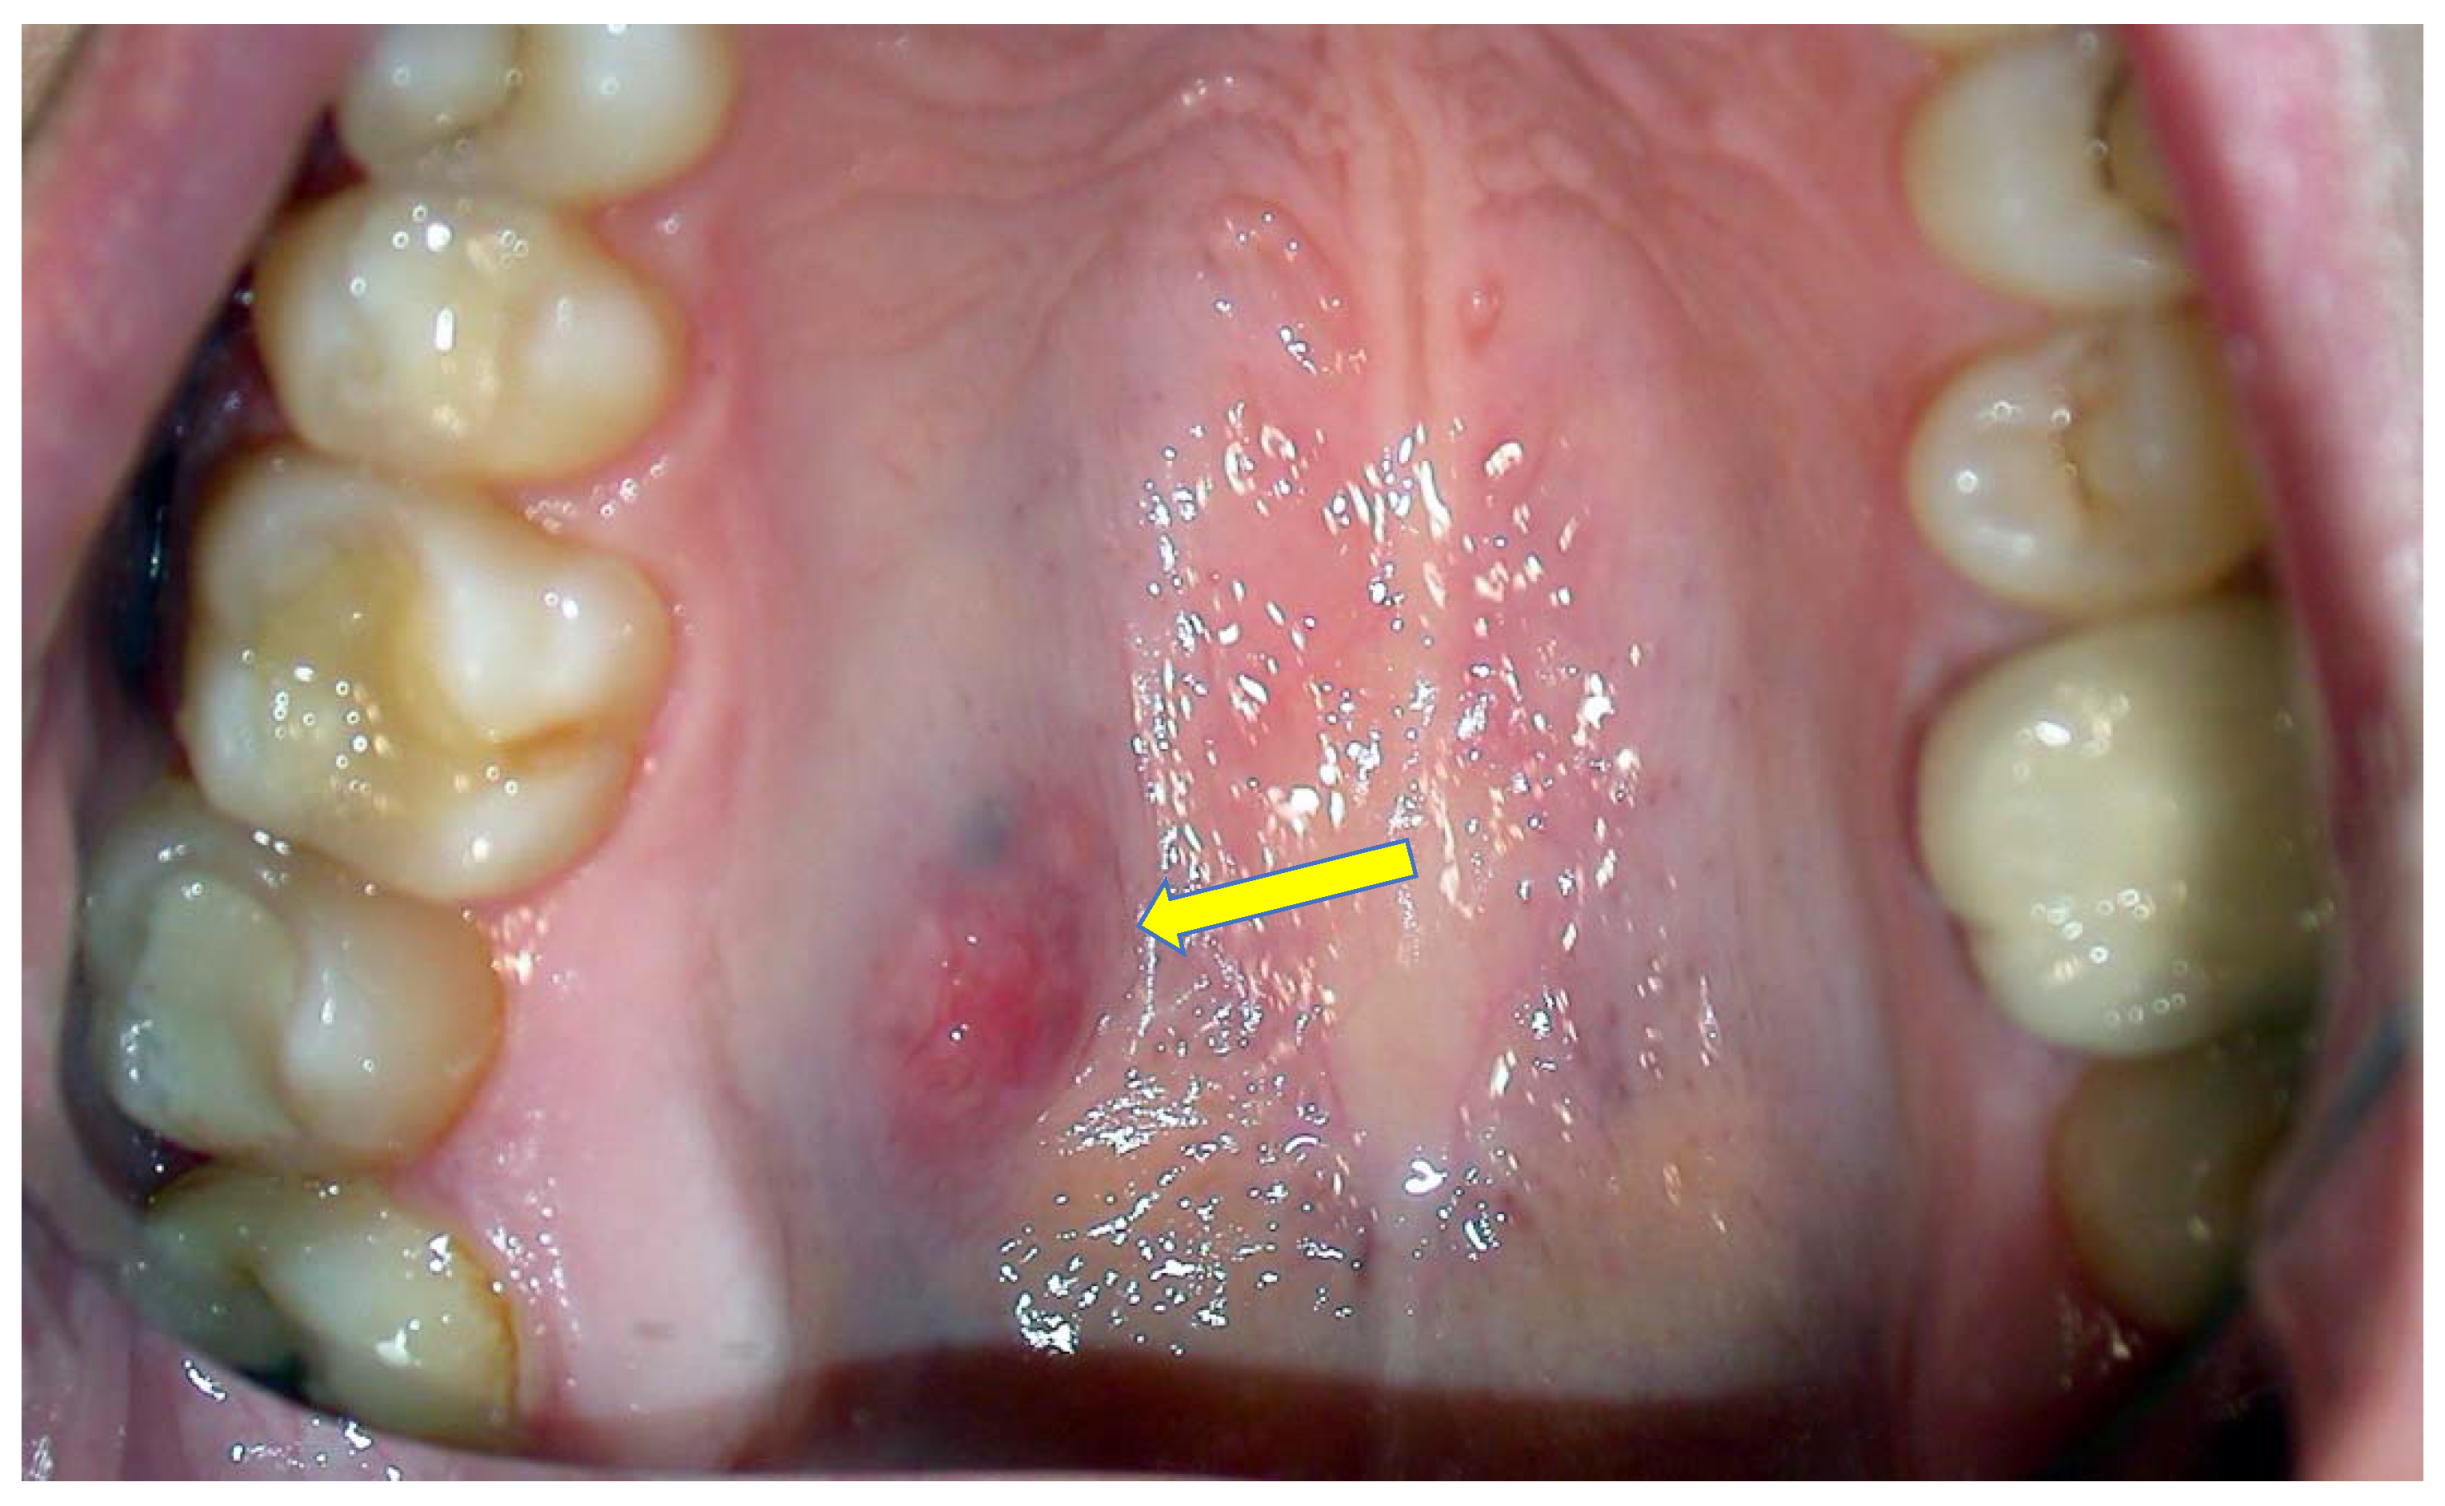

Browse high-quality images of cavity teeth to understand how tooth decay appears in its various stages. View detailed dental photos illustrating plaque buildup, enamel erosion, and common signs of dental caries. Use these visual references to identify potential oral health issues early and learn when it is time to consult your dentist for professional cavity treatment and prevention.